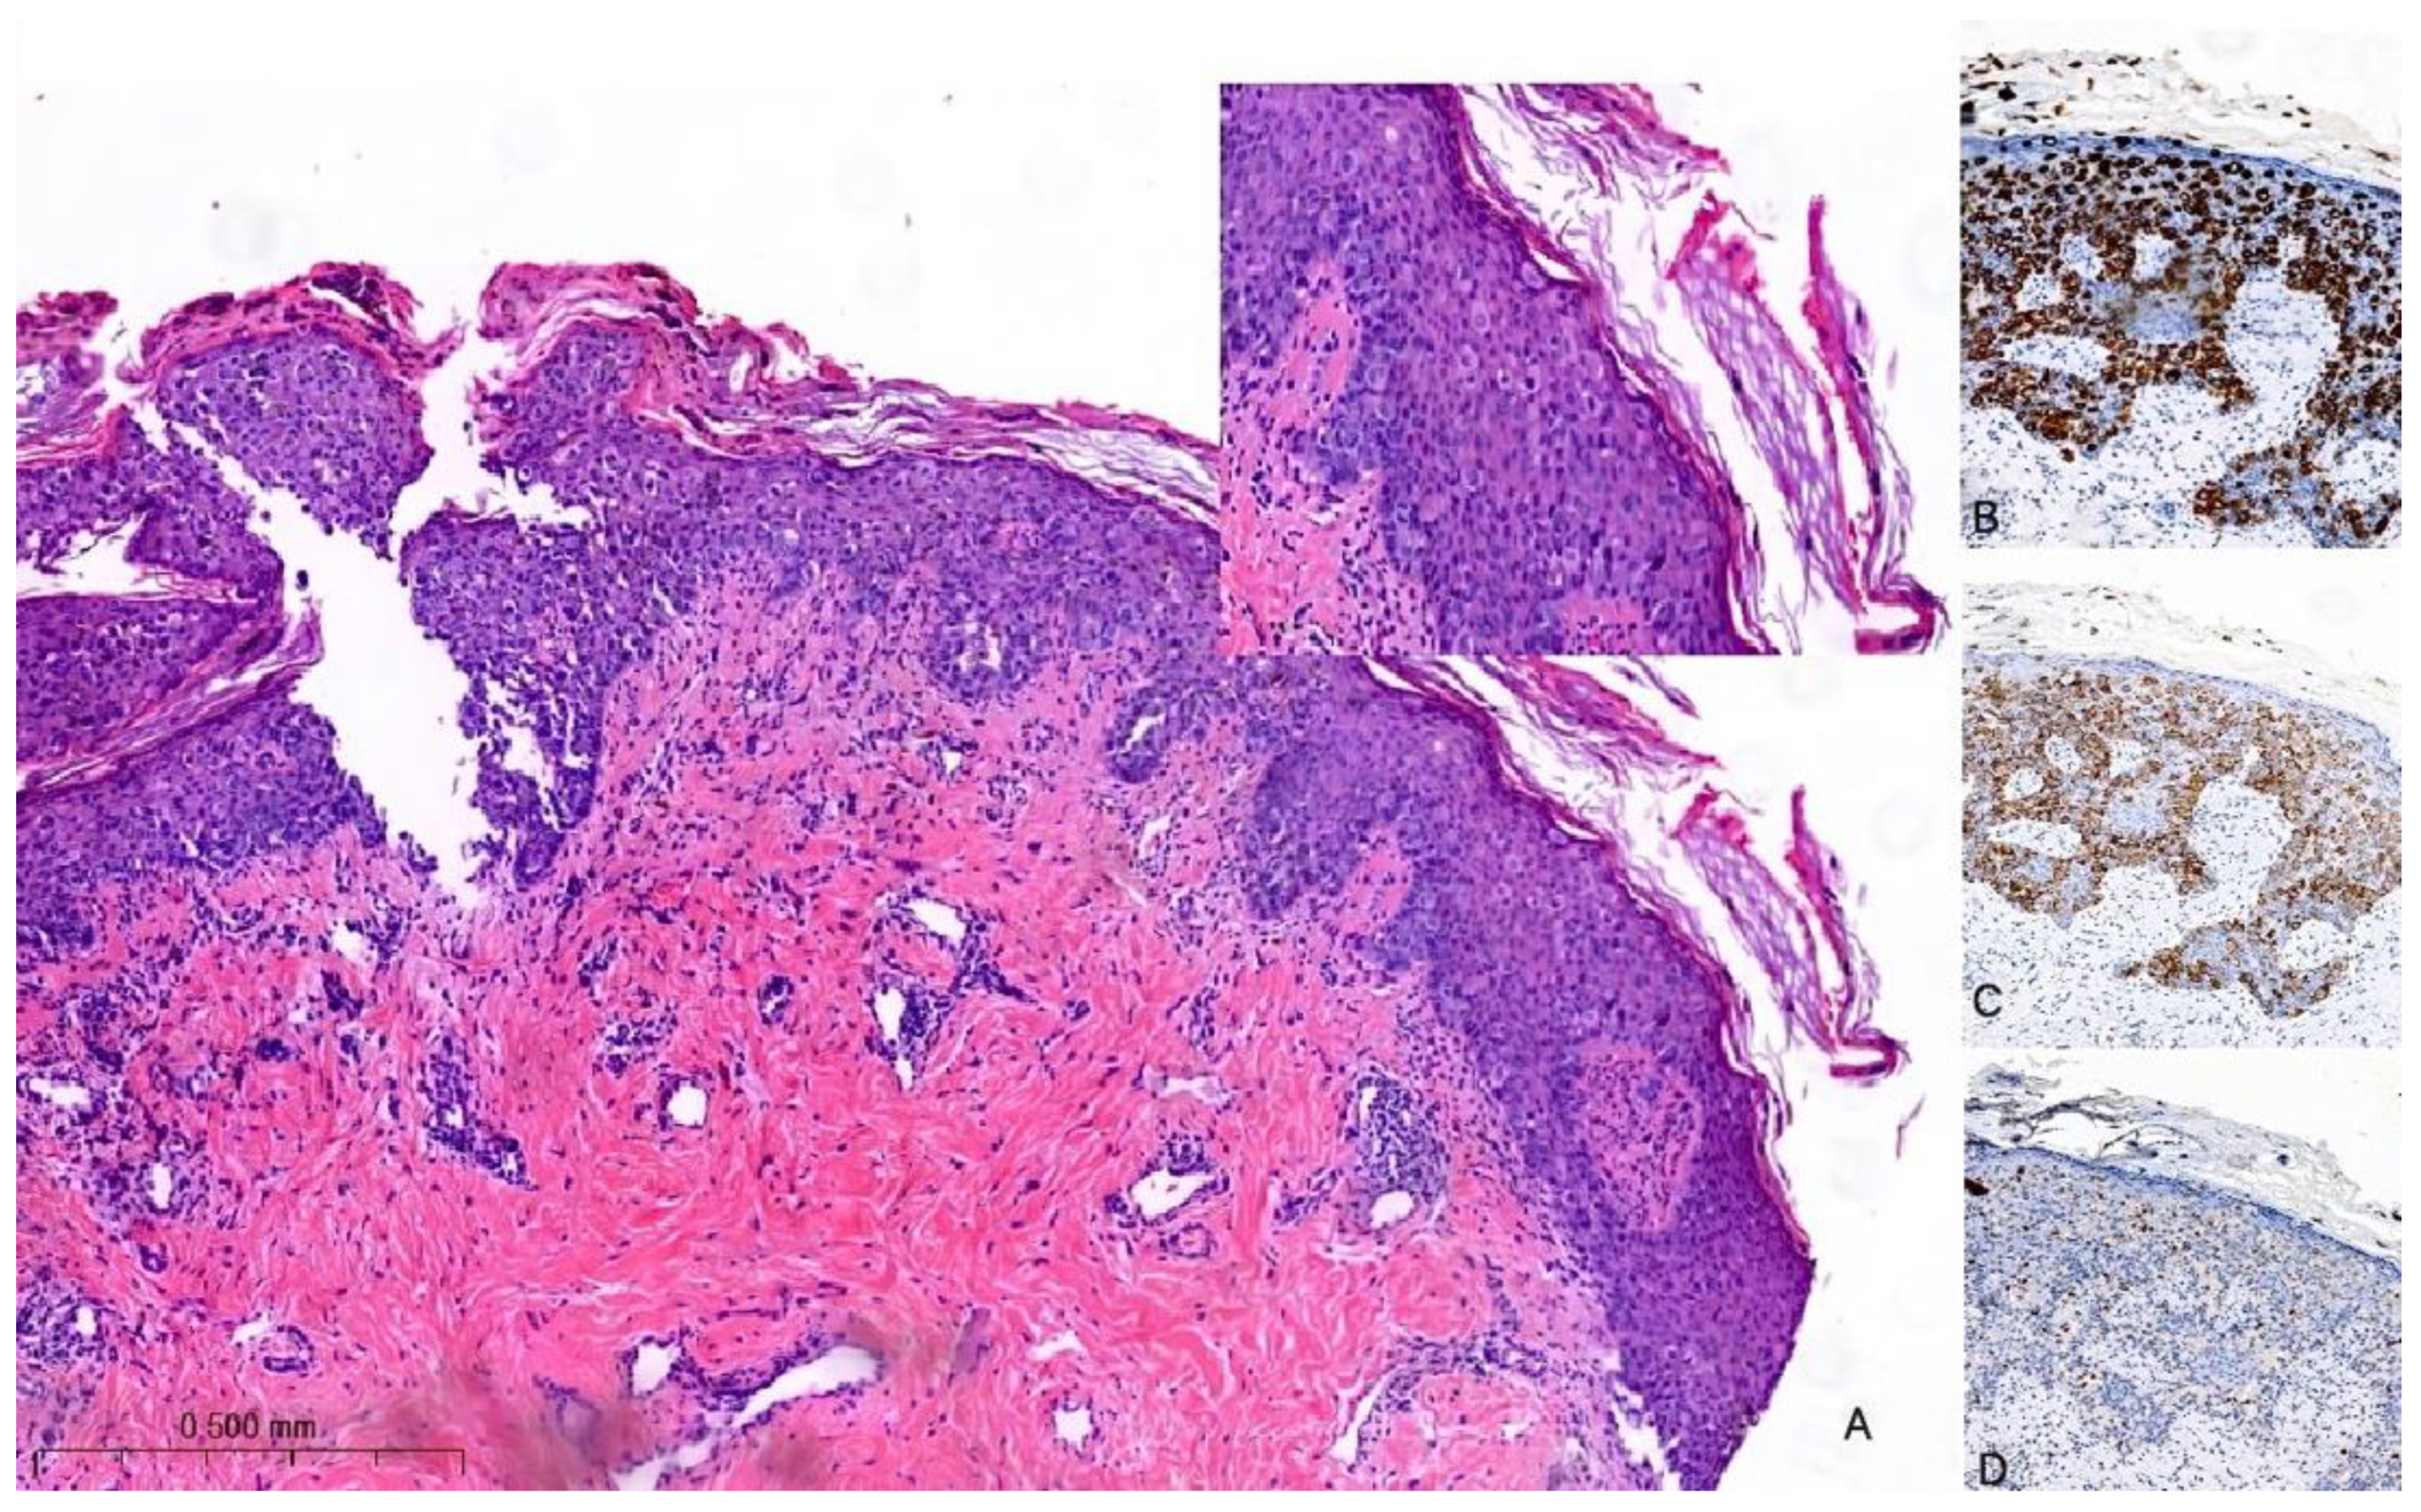

The histological hallmark of MPD is the presence of large intraepidermal epithelial cells (i.e., PC) with abundant pale cytoplasm, pleomorphic nuclei, and prominent nucleoli [27,28] (Figure 2A). PC can be found as solitary elements or in clusters dispersed throughout the epidermis and exhibit variable mitotic activity. The formation of glandular structures is infrequent. In 4–8% of cases, PC may extend into the dermis with their cytological characteristics remaining akin to those observed in the epidermis. Notably, there is a distinct demarcation between the infiltrating PC and the underlying BC with the possibility of a concomitant lymphocytic infiltrate in the interface [29]. To differentiate MPD from other malignant processes involving the skin (e.g., Bowen disease, inflammatory BC, melanoma in situ, or squamous cell carcinoma in situ), immunohistochemistry may be of help [30]. PC are typically positive for low-molecular-weight cytokeratins (e.g., CK7 and CAM5.2), but they can rarely be negative or only focally positive; however, it is important to note that pagetoid squamous cell carcinoma in situ can also express these markers. HER2 is overexpressed in 80–90% of cases (Figure 2B,C); ER and PgR are positive in approximately 40% and 30% of MPD cases, respectively. However, it is worth noting that PC usually share the same immune profile as the underlying carcinoma [24].

Figure 2.

Hematoxylin and eosin stain of histological sections of MPD (A): large intraepidermal cells with abundant pale cytoplasm and pleomorphic nuclei containing prominent nucleoli (Paget cells, PC) (H-E 100×, 400×). Immunohistochemical staining of PC with (B) CK7 antibody (200×) shows a strong PC positivity; with (C) HER2 antibody (200×) shows positive staining (membrane); and with (D) SOX10 antibody (200×) is used for the differential diagnosis with melanoma: PC are negative.

In a recent investigation, a novel immunohistochemical marker, TRPS1, was introduced and has since become widely adopted for confirming the diagnosis of MPD [31]. According to the findings reported in this study, TRPS1 expression was detected in 100% of cases of MPD. This breakthrough in immunohistochemistry has proven to be invaluable in distinguishing MPD from histological mimics, notably melanoma in situ and squamous cell carcinoma in situ. PC are negative for melanocytic markers (e.g., SOX10) (Figure 2D). Furthermore, it is worth noting that squamous cell carcinoma in situ is an exceedingly rare occurrence within the NAC. In such cases, the diffuse presence of TRPS1 within an intraepithelial pagetoid lesion arising in the nipple invariably confirms the diagnosis of MPD.